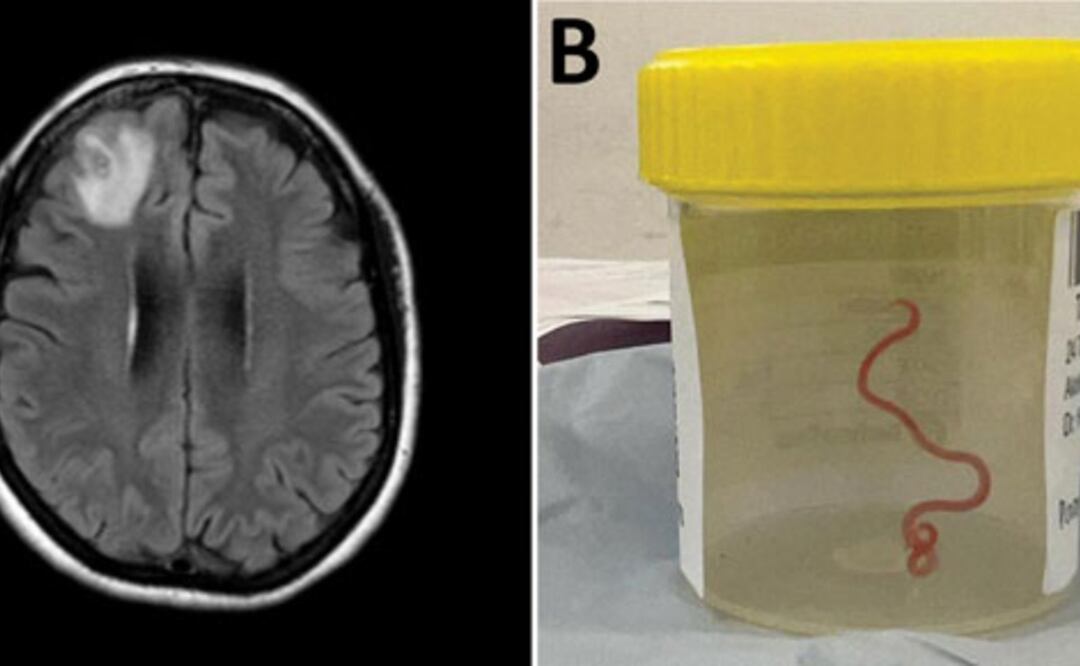

En 2022, la paciente se sometió a una resonancia magnética tras experimentar trastornos en la memoria y depresión. Las imágenes del cerebro de la paciente revelaron que la mujer tenía una lesión atípica en el lóbulo frontal derecho.

Un neurocirujano del Hospital de Canberra exploró la anomalía y fue entonces cuando se encontró la inesperada lombriz intestinal de ocho centímetros.

El parásito fue extraído, vivo y retorciéndose, de la paciente durante de una cirugía cerebral, de la que no se precisa la fecha, y actualmente la mujer continúa siendo examinada por el equipo de especialistas en enfermedades infecciosas y cerebro.